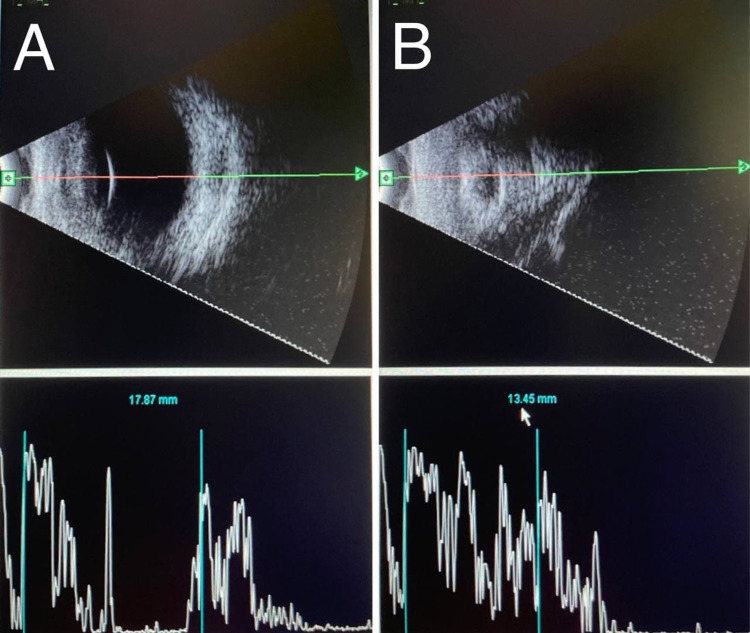

During multiple follow up later, clinical examination of the right eye (OD) was completely normal while the left eye (OS) started to regress and it becomes smaller in size with a clear cornea, 360° synechia, shallow anterior segment, multiple fibrous retrolental membranes with cataract, and no view to the fundus. Therefore, a repeated B-scan was planned, which revealed a normal examination of the right eye (OD) with an axial length of 17.87 mm while the left eye (OS) showed resolving retinal detachment with a short shrunken eye, marked ocular wall thickening and the axial length was 13.45 mm, which is consistent with prephthisical changes; hence, vitreoretinal team’s opinion was against any surgical intervention and a referral for oculoplastic clinic was done for ocular prosthesis later on (Figures 5A, 5B).

Figure 5. A repeated B-scan: (A) Right eye (OD): normal, the axial length is 17.78 mm. (B) Left eye (OS): shorth shrunken eye, marked ocular wall thickening, no retinal detachment and the axial length is 13.45 mm, which is consistent with prephthisical changes.